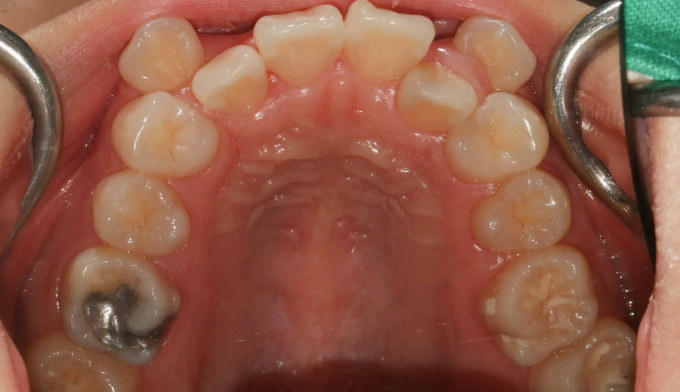

돌출입 정도는 약하지만, 공간이 매우 부족하여 덧니가 명확한 케이스 입니다.

치아 배열을 위한 공간이 많이 필요하기 때문에 발치를 통하여 공간을 먼저 확보하였습니다.

발치가 필요한 경우, 일반적으로 덧니인 송곳니보다는 작은어금니를 발치합니다. 가장 쓰임이 적고 덜 중요한 치아이기 때문입니다. 하지만 발치치아는 사람마다 그리고 케이스마다 달라집니다.